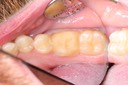

Kyle Chock #19 prep